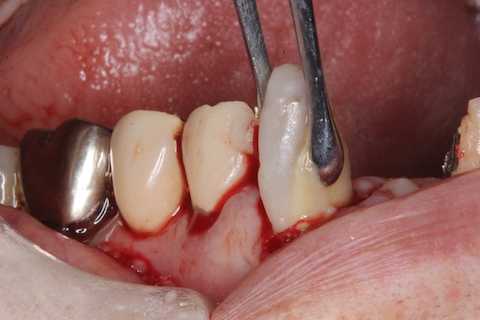

前回 ​のつづきで、再植と化粧をする。さすがに歯なしでは寂しい。

普通にズブズブと抜歯窩に再建した歯根を挿入する。

あとは接着固定しながら、歯冠を再建していく。